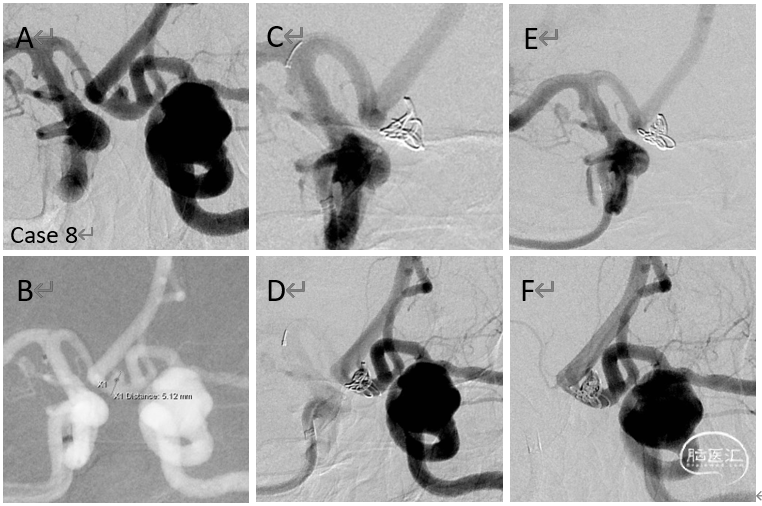

病例8

前交通动脉瘤单纯栓塞术

颈内动脉床突段脑动脉瘤二期处理

病例9

破裂的前交通动脉瘤急性单纯栓塞

(瘤颈)后二期支架植入

病例10

栓塞的破裂的前交通动脉瘤

(转入)致密栓塞之后二期给予支架植入